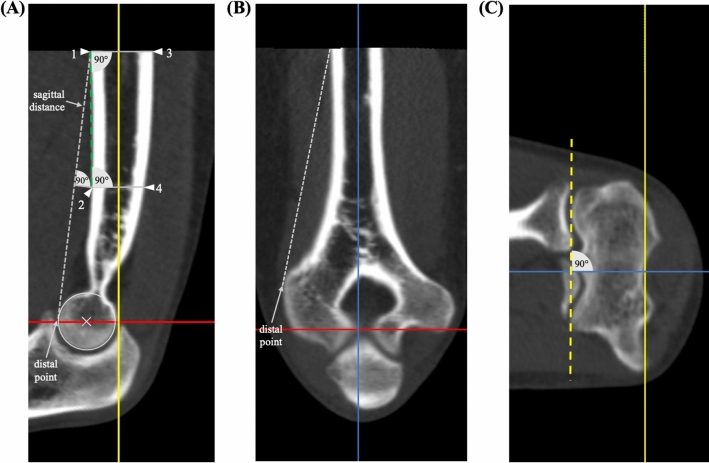

Fig. 1.

CT standard planes and determination of humeral shaft axis. The determination of the humerus shaft axis as applied for defining the standard planes is described in the section ‘humerus shaft axis’ and is depicted in this figure (A). The determination of the coronal humerus shaft axis (B) is achieved via the same approach as described for the sagittal view. The ‘distal point’ is defined as the most volar location on the trochlea in the sagittal view and the most lateral location on the lateral epicondyle in the coronal view and serves for determination of the sagittal distance. Red line: axial plane, bisects the trochlea in the sagittal view. Yellow line: coronal plane, humerus shaft axis in the sagittal view and parallel to the joint surface (dashed yellow line) in the axial view (C). Blue line: sagittal plane, humerus shaft axis in the coronal view. Grey dashed line: sagittal distance. Green dashed line: connection of point 1 and 2. Circle: trochlea surface (color figure online)

CT standard planes

The coronal plane and is adjusted parallel to the joint line in the axial view (Fig. 1C) and as a bisecting line of the trochlea in the sagittal view (Fig. 1A). In the sagittal view (Fig. 1A), the coronal plane parallels the longitudinal axis of the humerus shaft. The sagittal plane is adjusted parallel to the longitudinal axis of the humerus shaft in the coronal view (Fig. 1B). In the axial view, the coronal and sagittal plane are orthogonal to each other, whereas in the coronal view, the axial and sagittal plane and in the sagittal view, the coronal and axial plane are orthogonal to each other.

Humerus shaft axis

The humerus shaft axis was defined using a ‘centerline by four points’ in the sagittal and coronal view using IMPAX EE software (AGFA Health Care, Mortsel, Belgium). The four points were adjusted according to a standardized method (Fig. 1A).

Sagittal view: Point 1 was defined as the most proximal point on the volar outer cortical surface of the humerus shaft. Point 2 was adjusted perpendicular to the middle of the sagittal distance which was defined as the distance between point 1 and the most volar point on the trochlea (distal point). Point 3 was adjusted on the dorsal outer cortical surface opposite to point 1 and perpendicular to a connecting line between point 1 and point 2. Point 4 was adjusted on the dorsal outer cortical surface opposite to point 2 and perpendicular to a connecting line between point 1 and point 2.

Coronal view: Point 1 was defined as the most proximal point on the lateral outer cortical surface of the humerus shaft. Point 2 was adjusted perpendicular to the middle of the distance between point 1 and the most lateral point of the lateral epicondyle (distal point). Point 3 and point 4 were located on the medial outer cortical surface of the humerus and were adjusted as described for the sagittal view.